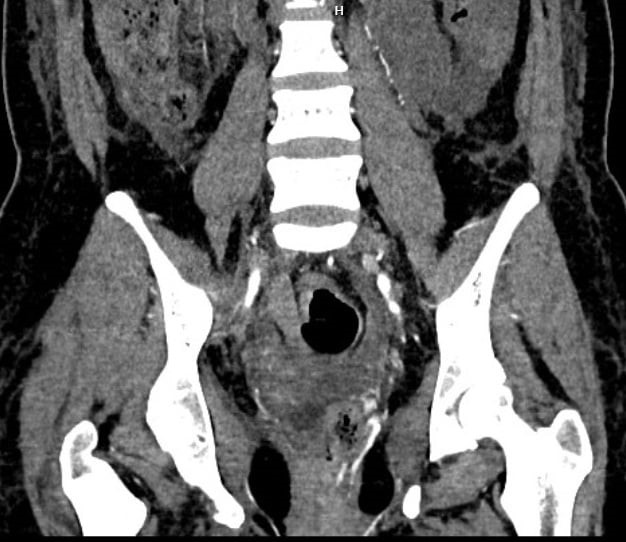

Trước diễn tiến ngày càng nguy kịch, các bác sĩ bệnh viện tỉnh đã hội chẩn trực tuyến qua điện thoại với Trung tâm Cấp cứu A9, Bệnh viện Bạch Mai. Kết quả buổi hội chẩn từ xa qua Telehealth, bệnh nhân được chuyển tuyến cấp cứu lên Trung tâm Điện quang, Bệnh viện Bạch Mai. Tại Bạch Mai, các bác sĩ của Trung tâm Cấp cứu A9 và Trung tâm Điện quang lập tức hội chẩn cấp cứu để đưa ra phương án chẩn đoán và điều trị cho người bệnh. Kết quả chụp MSCT cho thấy, bệnh nhân bị tổn thương chảy máu từ mạch máu quanh trực tràng. Những quyết định, phác đồ xử trí được hoạch định chớp nhoáng, bởi lẽ, nếu muộn hơn một chút thôi, bệnh nhân sẽ dẫn tới biến chứng rối loạn đông máu, suy gan, suy thận và tổn thương não,…

Hình ảnh thoát thuốc vị trí động mạch tử cung trái và quanh trực tràng